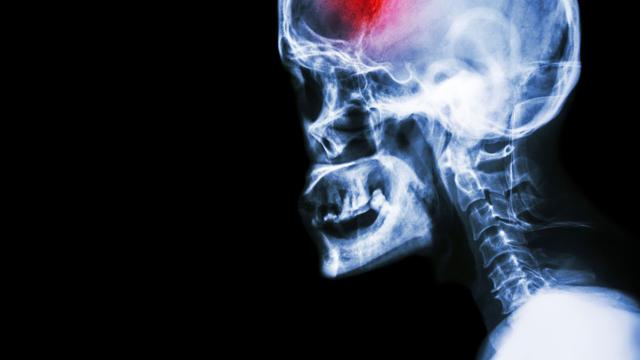

Salah satu jenis stroke adalah akibat adanya perdarahan. Dari sekian banyak penyebab penyakit itu, salah satunya adalah aneurisma otak.

Aneurisma sendiri bisa diartikan sebagai pelebaran dinding pembuluh darah akibat lemahnya struktur dinding tersebut. Hal ini umumnya terjadi pada pembuluh arteri seperti di otak, jantung, aorta, arteri poplitea, dan lain-lain. Kondisi itu membuat organ tersebut seakan membentuk "balon" yang bisa pecah sewaktu-waktu.

Meskipun begitu, salah satu yang paling berbahaya dan mematikan adalah aneurisma otak. Menurut dokter spesialis saraf di RS Pondok Indah - Pondok Indah, Rubiana Nurhayati, kondisi tersebut diperkirakan terjadi pada 1 dari 100 orang.

Yang berbahaya adalah ketika aneurisma otak pecah. Masalah itu bisa membuat darah merendam otak dan mengakibatkan stroke. Sayangnya, kondisi tersebut bisa terjadi tanpa disadari gejalanya.

Ketika aneurisma otak sudah pecah, seseorang bisa terkena stroke, koma, bahkan menyebabkan kematian. Maka dari itu, pencegahan dengan skrining penting agar seseorang dengan kondisi itu tidak mengalami hal-hal yang lebih fatal.